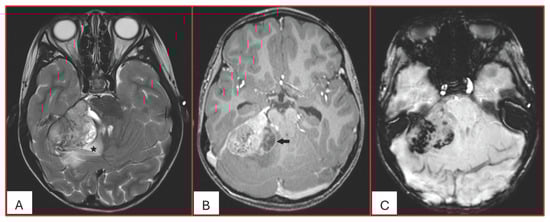

Figure 1. Five-year-old male with ATRT-MYC subgroup. (A). Axial T2-weighted image demonstrates a large extra-axial mass in the posterior fossa centered at the right cerebellopontine angle of intermediate heterogeneous signal. There is surrounding vasogenic edema (star) and mass effect. (B). Axial post contrast T1-weighted image shows heterogeneous enhancement with eccentric peripherally enhancing cystic component (arrow). (C). Axial SWI demonstrates multiple internal foci of susceptibility reflecting hemorrhagic content (no calcifications on the concurrent CT). This tumor was associated with leptomeningeal spread at the time of diagnosis into the internal auditory canals and along the cerebellar folia.